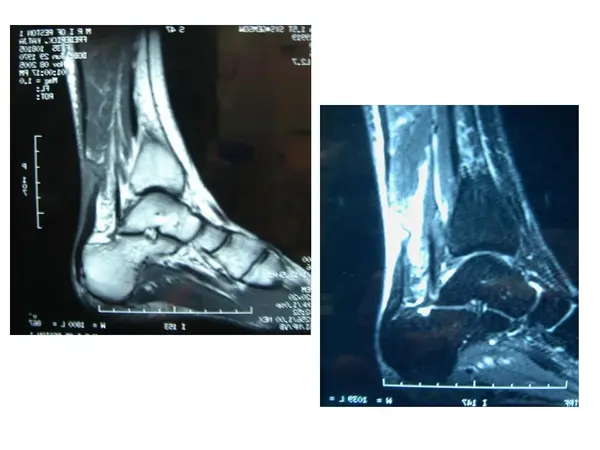

In diagnosing an Achilles tendon rupture, the foot and ankle surgeon will ask questions about how and when the injury occurred and Achilles tendon rupture whether the patient has previously injured the tendon or experienced similar symptoms. The surgeon will examine the foot and ankle, feeling for a defect in the tendon that suggests a tear. Range of motion and muscle strength will be evaluated and compared to the uninjured foot and ankle. If the Achilles tendon is ruptured, the patient will have less strength in pushing down (as on a gas pedal) and will have difficulty rising on the toes.

The diagnosis of an Achilles tendon rupture is typically straightforward and can be made through this type of examination. In some cases, however, the surgeon may order an MRI or other advanced imaging tests.